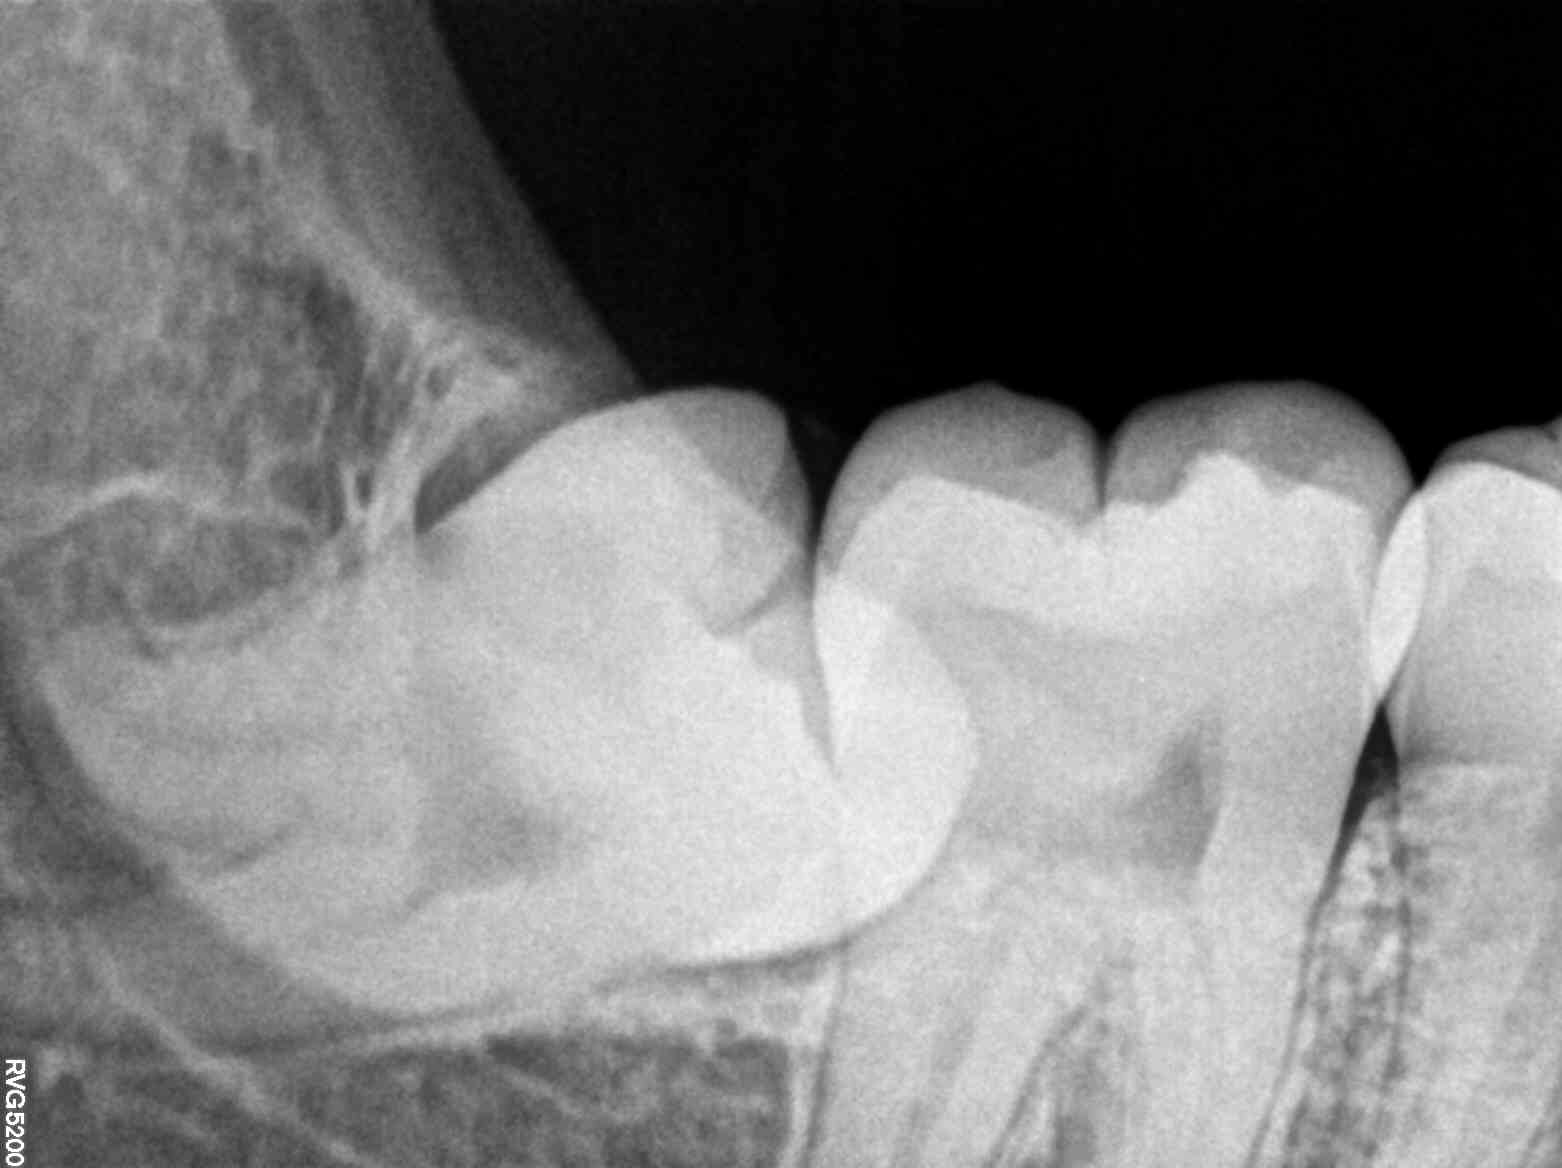

The X-ray process was quick and non-invasive, a relief for Ananya, who had worried about discomfort. Within minutes, Dr. Kapoor was able to show her detailed images of her teeth and jaw. It turned out that Ananya had a developing cavity and a minor misalignment in her jaw, which were causing her pain. These issues, if left untreated, could have led to more severe problems.

Dr. Kapoor shared a case study of a young boy named Rohan, who had been suffering from recurrent toothaches. Traditional examinations failed to pinpoint the problem, but an X-ray revealed an impacted wisdom tooth pressing against his molars. The early detection spared Rohan from future complications and ensured a swift recovery.